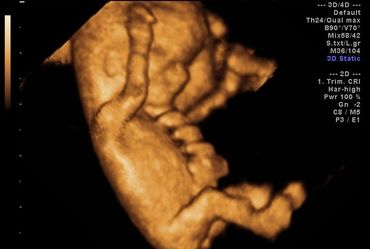

All our providers do their own ultrasounds in the office during your visit. We are known for our ultrasounds and do at least four with each pregnancy. And we can record your ultrasound on a USB device for you to take home and share!